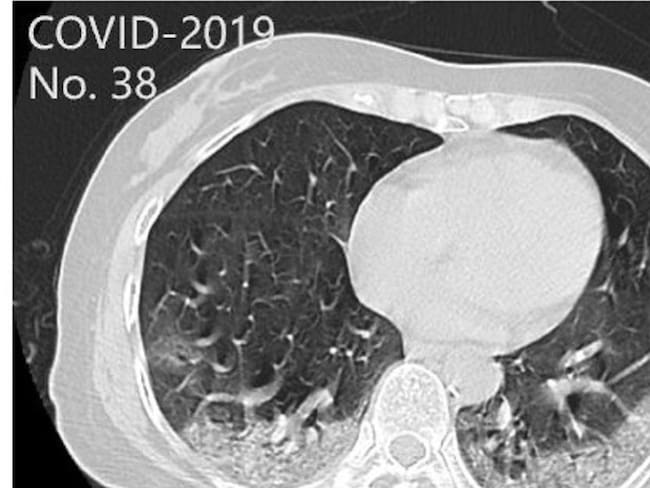

Es un sistema de inteligencia artificial creado por ingenieros santandereanos donde con solo una radiografía Rayos X o una tomografía que se insertan a una plataforma en línea, en menos de 30 segundos este detecta si el paciente sospechoso fue infectado o no con coronavirus. Así lo aseguró el ingeniero egresado de la UIS, Helver Álvarez.

Explicó que de mil pruebas que se han realizado el 95% han sido asertivas y se espera que en las próximas semanas sea utilizado por hospitales y el laboratorio de la UIS que están habilitados por el Instituto Nacional de Salud para la realización de estas pruebas.

El ingeniero señaló que este sistema de inteligencia artificial está activo y en línea para cualquier persona que desee descartar si es sospechosos de la COVID-19.

Tendrá la asistencia de profesionales de la salud e ingenieros que llevarán el proceso hasta entregar los resultados. Dijo que el uso del sistema es gratuito y la idea es contribuir tecnológicamente al hallazgo de más casos positivos y evitar así el contagio de este virus en la región.

Cabe resaltar que el trabajo fue hecho por la empresa santandereana AC INGENIERÍA VIRTUAL y tuvo apoyo de la empresa brasilera IVARE para poner en funcionamiento el sistema.